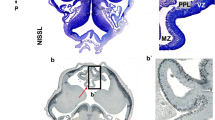

Periventricular pathway (PVP) system of the developing human cerebrum is situated medial to the intermediate zone in the close proximity to proliferative cell compartments. In order to elucidate chemical properties and developing trajectories of the PVP we used DTI in combination with acetylcholinesterase histochemistry, SNAP-25 immunocytochemistry and axonal cytoskeletal markers (SMI312, MAP1b) immunocytochemistry on postmortem paraformaldehyde-fixed brains of 30 human fetuses ranging in age from 10 to 38 postconceptional weeks (PCW), 2 infants (age 1–3 months) and 1 adult brain. The PVP appears in the early fetal period (10–13 PCW) as two defined fibre bundles: the corpus callosum (CC) and the fetal fronto-occipital fascicle (FOF). In the midfetal period (15–18 PCW), all four components of the PVP can be identified: (1) the CC, which at rostral levels forms a voluminous callosal plate; (2) the FOF, with SNAP-25-positive fibers; (3) the fronto-pontine pathway (FPP) which for a short distance runs within the PVP; and (4) the subcallosal fascicle of Muratoff (SFM) which contains cortico-caudate projections. The PVPs are situated medial to the internal capsule at the level of the cortico-striatal junction; they remain prominent during the late fetal and early preterm period (19–28 PCW) and represent a portion of the wider periventricular crossroad of growing associative, callosal and projection pathways. In the perinatal period, the PVPs change their topographical relationships, decrease in size and the FOF looses its SNAP-25-reactivity. In conclusion, the hitherto undescribed PVP of the human fetal cerebrum contains forerunners of adult associative and projection pathways. Its transient chemical properties and relative exuberance suggest that the PVP may exert influence on the development of cortical connectivity (intermediate targeting) and other neurogenetic events such as neuronal proliferation. The PVP’s topographical position also indicates that it is a major site of vulnerability in hypoxic–ischaemic perinatal brain injury.